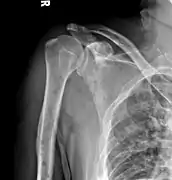

The diagnostic examination of a person with suspected multiple myeloma typically includes a skeletal survey. This is a series of X-rays of the skull, axial skeleton, and proximal long bones. Myeloma activity sometimes appears as "lytic lesions" (with local disappearance of normal bone due to resorption) or as "punched-out lesions" on the skull X-ray ("raindrop skull"). Lesions may also be sclerotic, which is seen as radiodense.[70] Overall, the radiodensity of myeloma is between −30 and 120 Hounsfield units (HU).[71] Magnetic resonance imaging is more sensitive than simple X-rays in the detection of lytic lesions, and may supersede a skeletal survey, especially when vertebral disease is suspected. Occasionally, a CT scan is performed to measure the size of soft-tissue plasmacytomas. Bone scans are typically not of any additional value in the workup of people with myeloma (no new bone formation; lytic lesions not well visualized on bone scan).

Multiple myeloma in the upper arm